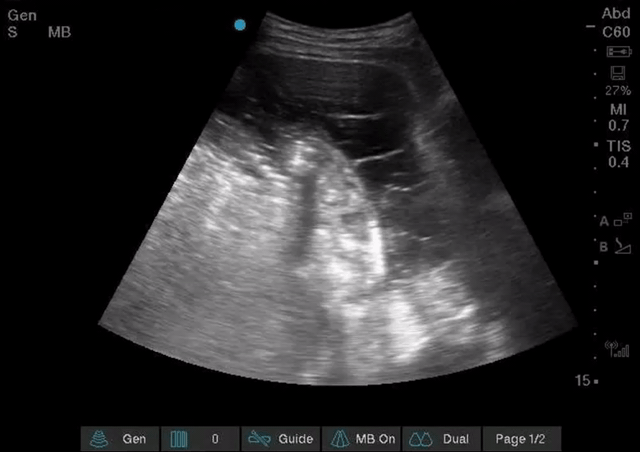

Complicated ascites: Though most of the abdominal free fluid encountered in IM is due to ascites from portal hypertension, exudative causes such as inflammatory, traumatic, and infectious collections that are non-gravity dependent or isolated to one part of the abdomen are also possible. Therefore it is important to not only look for abdominal fluid but also note its appearance as well. Notice in the images below the webbed and hazy appearance of the fluid; this patient had frankly purulent ascites requiring multiple abdominal drains.